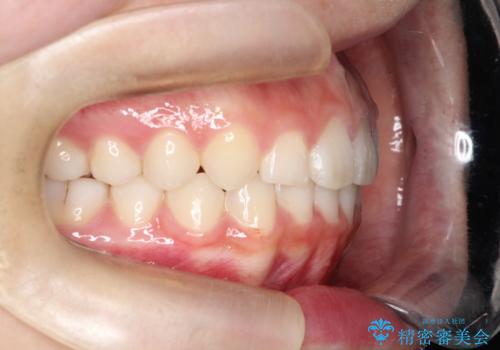

【インビザライン】出っ歯を引っ込めたい。

- 前歯の隙間と、出っ歯に見えることを主訴に来院されました。

できるだけ目立たない装置をご希望されましたので、インビザラインにて治療を行いました。

治療中は、できるだけ前歯を下げることができるように”顎間ゴム”を使用します。

”顎間ゴム”を利用することで、奥歯を後ろに動かす力を強めることができます。